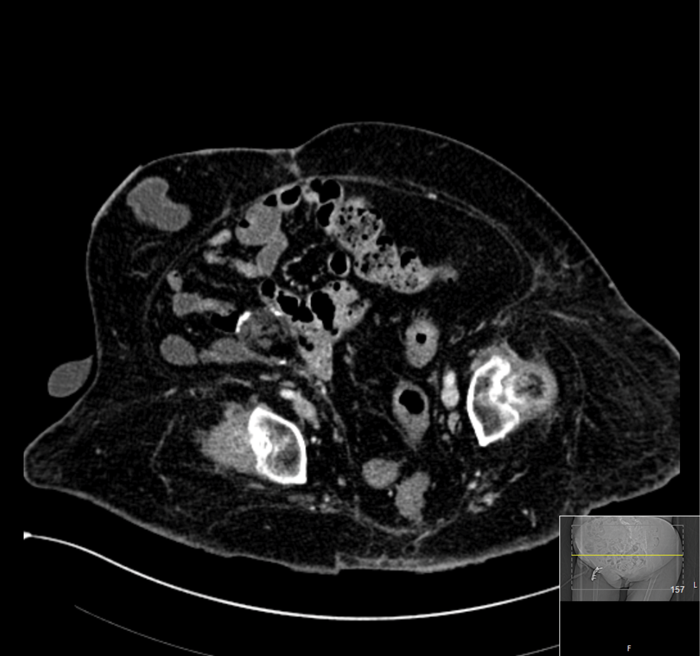

Fragmentation was achieved but a postoperative CT demonstrated a significant residual burden (Figure 2).

Figure 2: CT scan immediately postoperative.